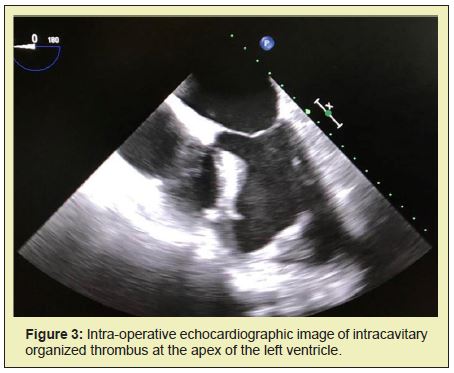

Intraoperative transoesophageal echocardiogram (TEE)also showed an intracavitary organized thrombus at the apex of the left ventricle that was left untouched (Figure 3), to be posteriorly treated conservatively with anticoagulation. The patient was transported to the intensive care unit (ICU) in a stable condition, was extubated on post-operative day two and discharged on day eleven.